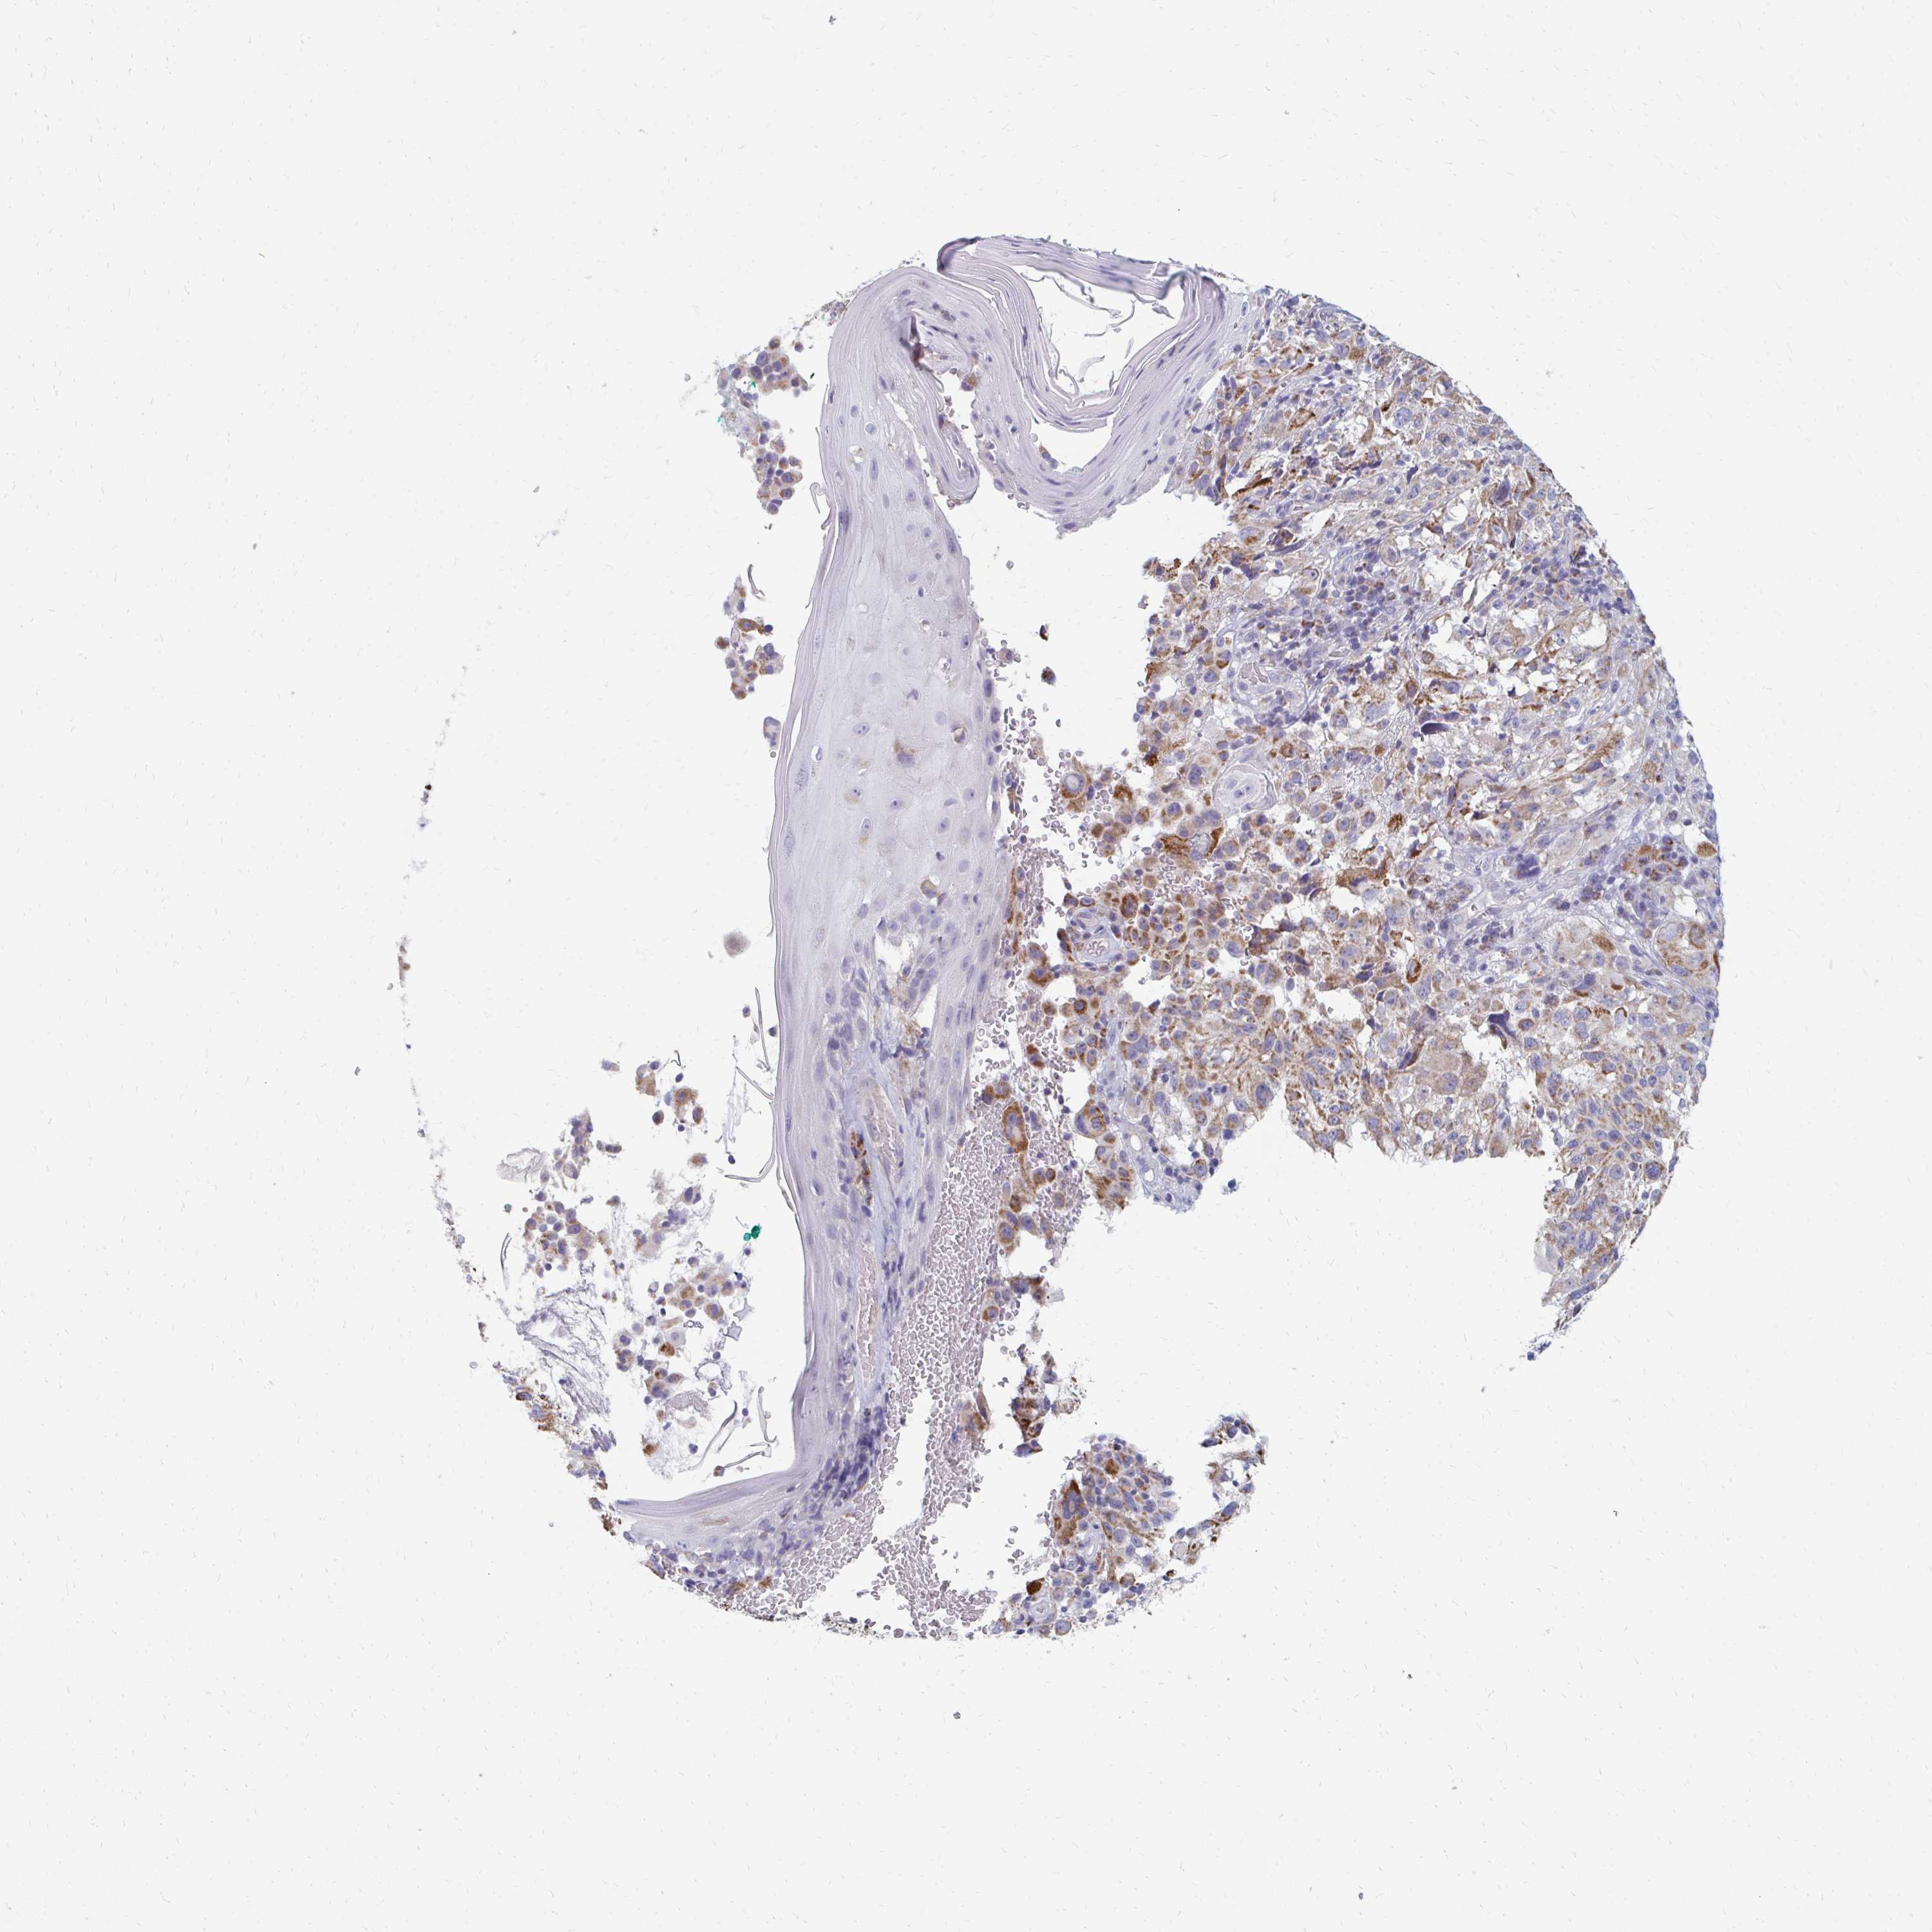

MELANOMA - Protein expressioni

A mouse-over function shows sample information and annotation data. Click on an image to view it in a full screen mode. Samples can be filtered based on level of antibody staining by selecting one or several of the following categories: high, medium, low and not detected. The assay and annotation is described here.

Note that samples used for immunohistochemistry by the Human Protein Atlas do not correspond to samples in the TCGA dataset.

Antibody stainingi

Antibody staining in the annotated cell types in the current human tissue is reported as not detected, low, medium, or high, based on conventional immunohistochemistry profiling in selected tissues. This score is based on the combination of the staining intensity and fraction of stained cells.

Each image is clickable and will lead to virtual microscopy that enables deeper exploration of all samples and also displays staining intensity scores, fraction scores and subcellular localization as well as patient and tissue information for each sample.

Antibody HPA060076

Staining

High

Medium

Low

Not detected

Intensity

Strong

Moderate

Weak

Negative

Quantity

>75%

75%-25%

<25%

None

Location

Nuclear

Cytoplasmic/membranous

Cytoplasmic/membranous,nuclear

Malignant melanoma, NOS

Malignant melanoma, Metastatic site